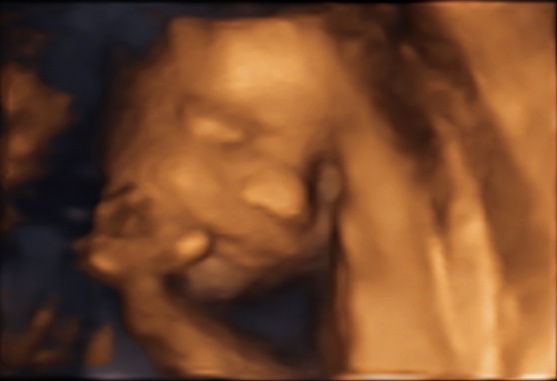

37 weken

Een echo na 37 weken.